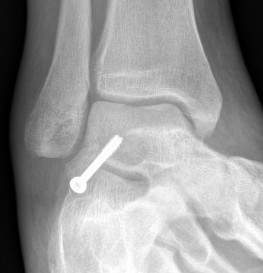

Operative Management

Indications

Large / displaced fragments

Intra-articular fracture with risk of subtalar OA

Options

1. ORIF - headless compression screw

2. Excision

Approach

Direct lateral approach to the talus

- lateral malleolus to base 4th metatarsal

- between peroneal tendons and extensor tendons

- can use image intensifier to mark incision

- excise fat over subtalar joint